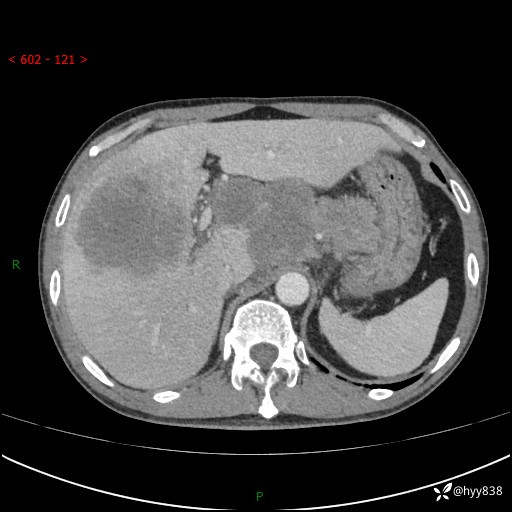

上腹部CT平扫+增强(两期)